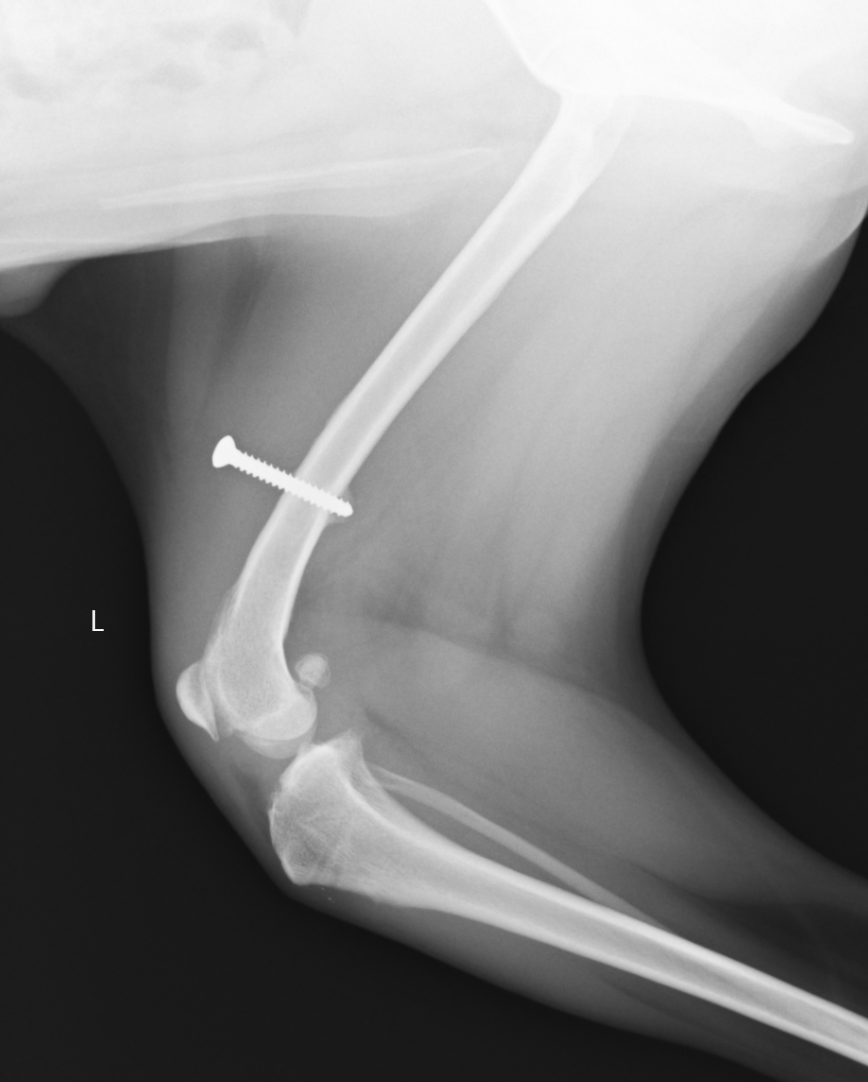

膝蓋骨滑落防止スクリュー:大腿骨にスクリューを打ち、4頭筋を制御することでパテラを落ちないようにする方法です。